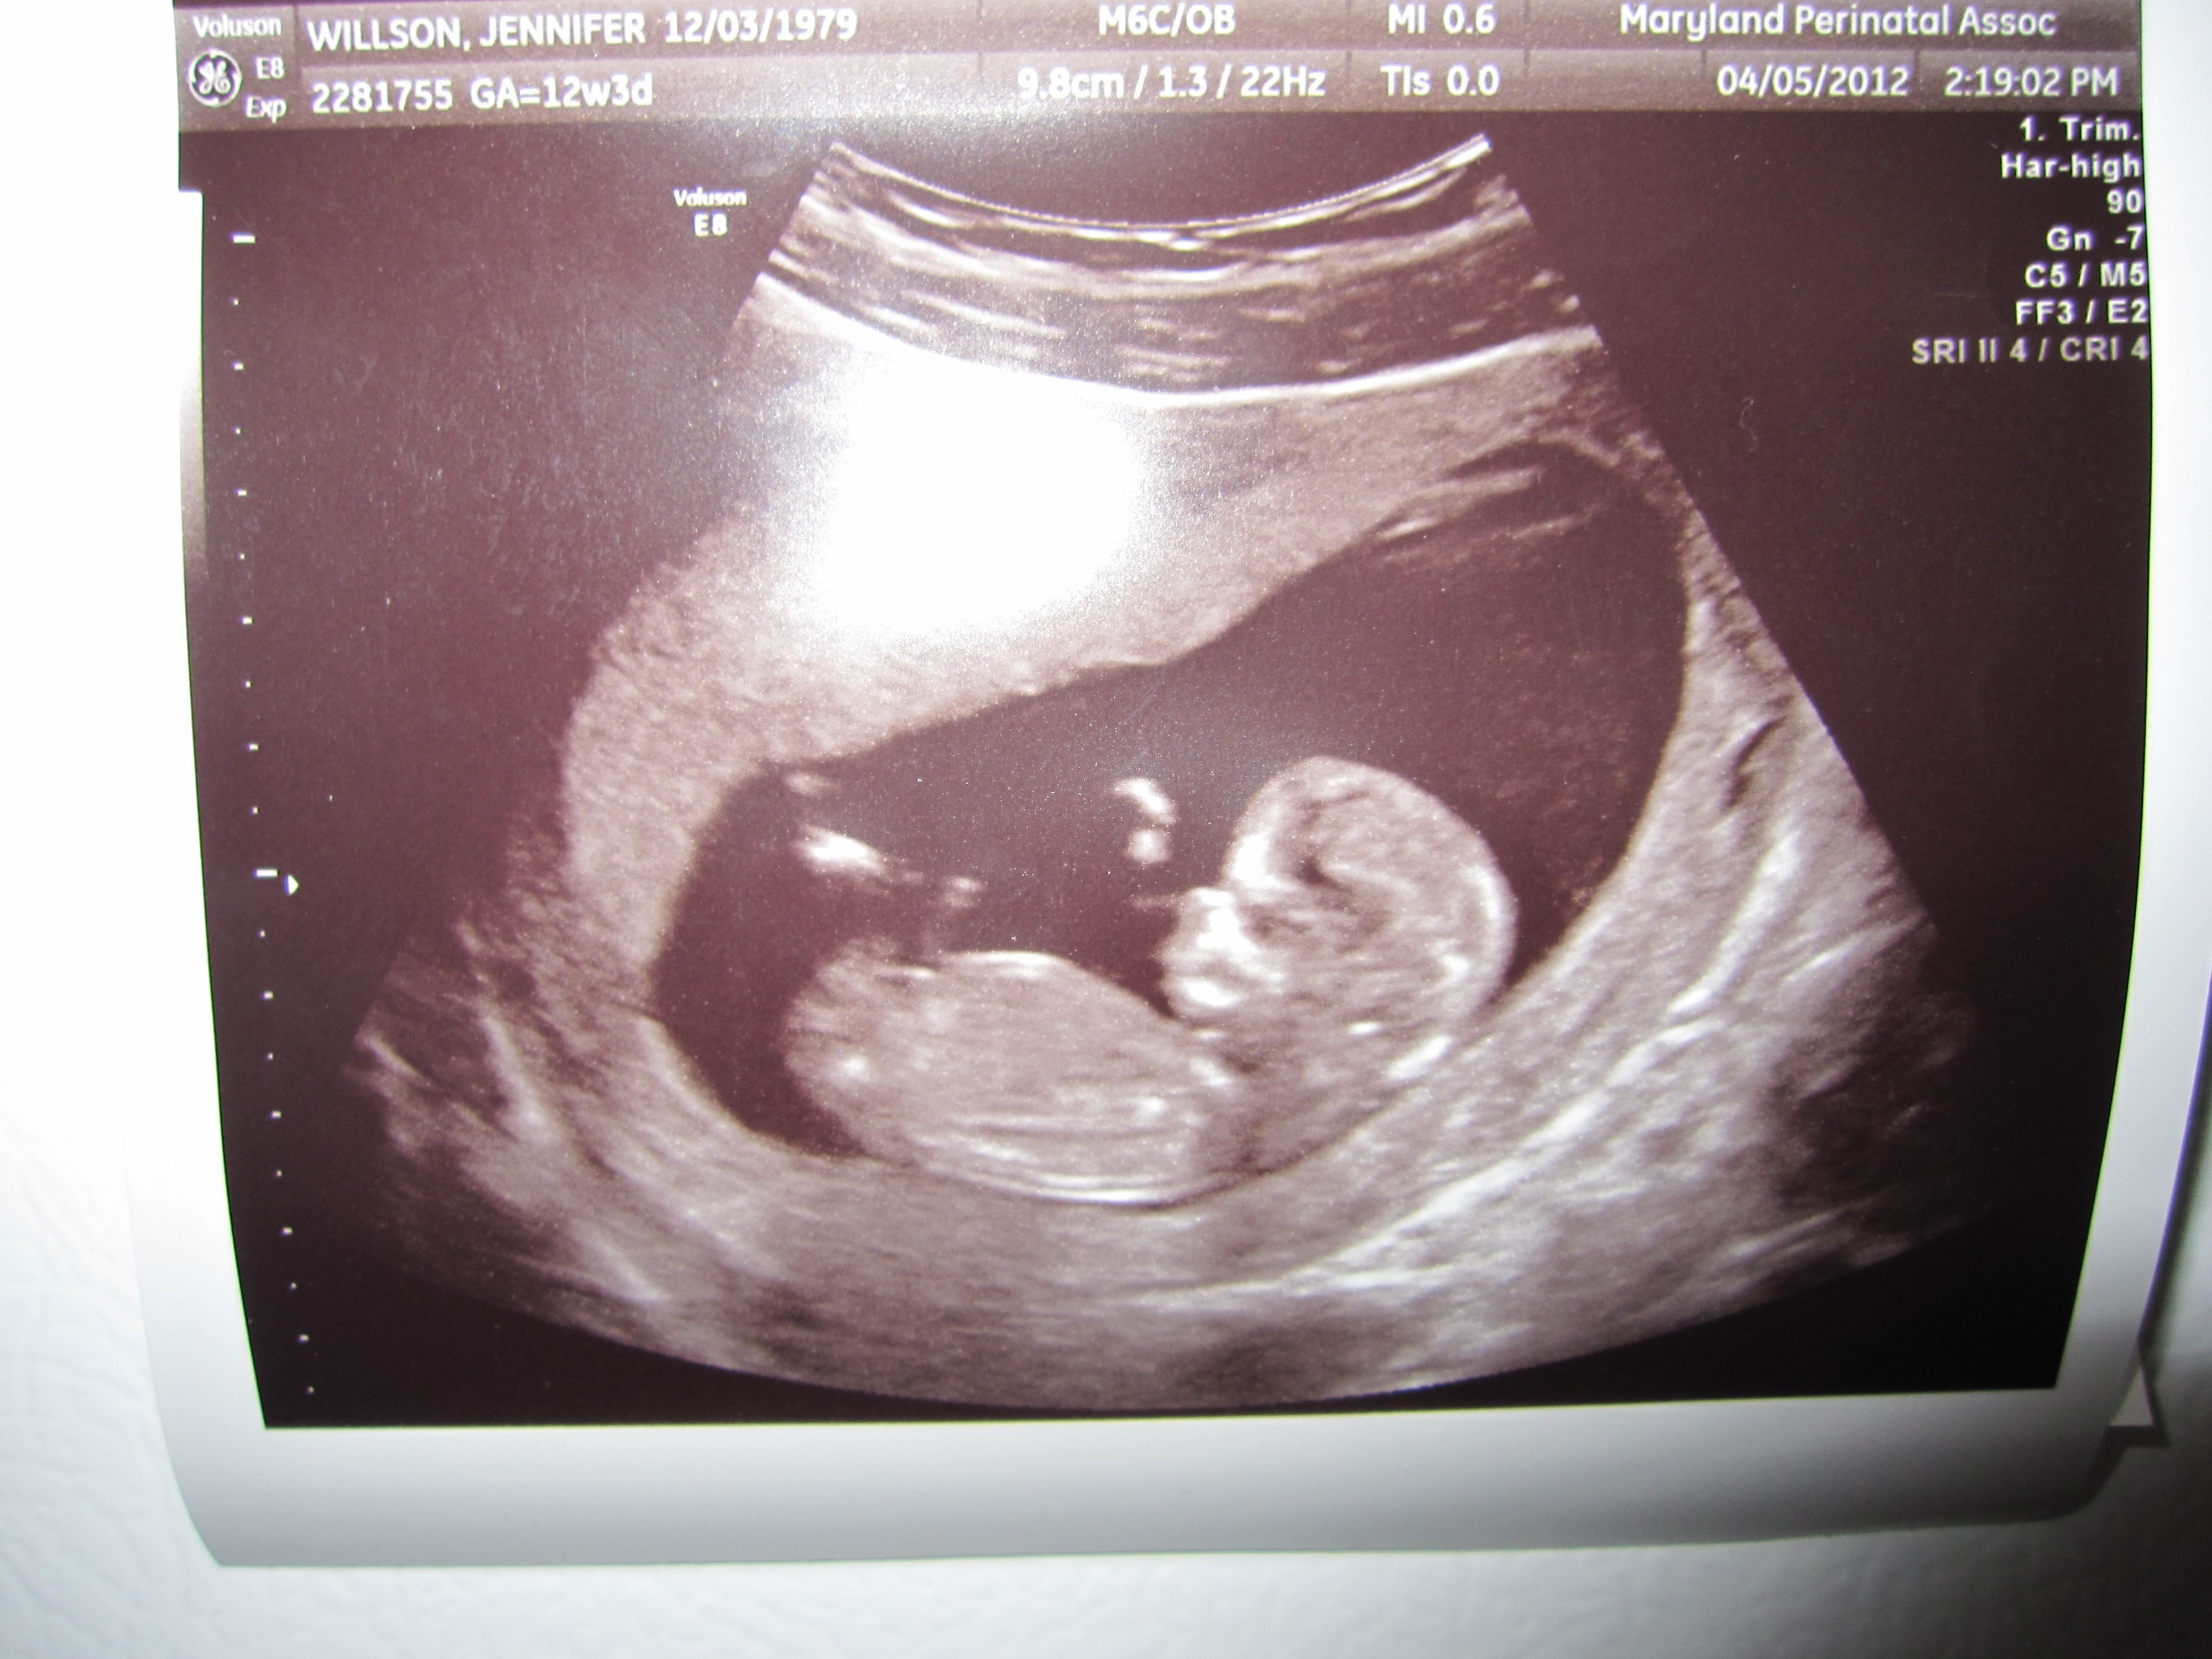

Yes folks, that is in fact another baby human in my uterus. That’s how far I’m willing to go to keep this blog alive! At least until the baby comes out and I have no time to do anything but wipe other people’s butts.

I know what you’re thinking: I am super dedicated to my readership (all 4 of you). So dedicated that I’m going to have this bébé all the way over in Austria, which means I’ll most likely have some big nurse named Helga barking at me in stern German to poooosh! And if that won’t make for good blog material, I don’t know what will.